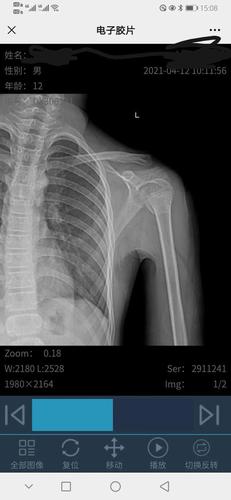

孩子摔伤,左肱骨近端骨折,是保守治疗还是动手术治疗好

左侧肱骨近端骨折

肱骨近端骨折图片

肱骨近端骨折

肱骨近端骨折分型

肱骨近端骨折neer分型